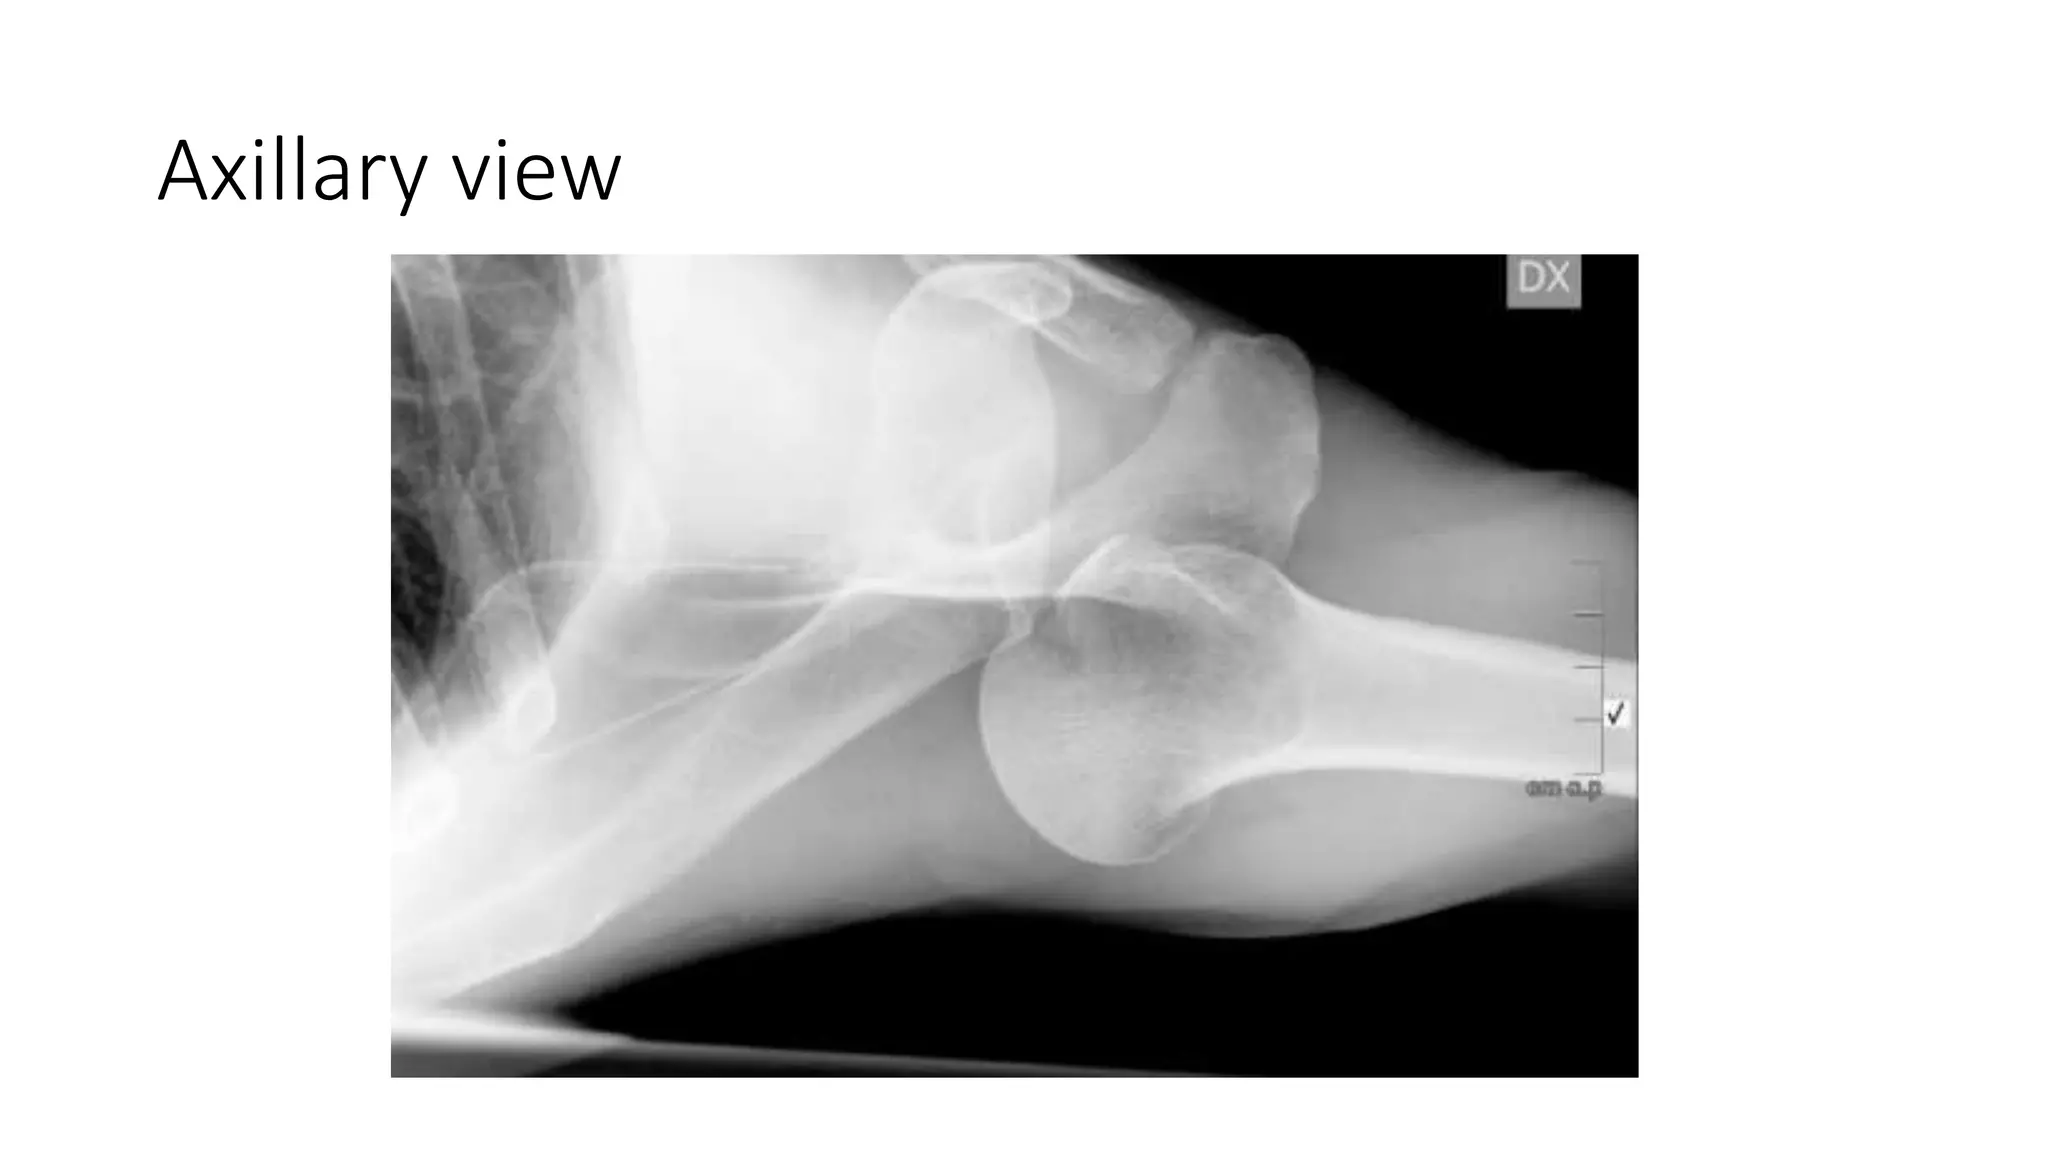

Axillary view

• Axillary lateral :- best view to demonstrate a dislocation.

Imaging Radiographs • true AP •scapular Y • axillary other helpful views • West Point view :- shows glenoid bone loss • Stryker view :- shows Hill-Sachs lesion • CT scan • helpful for evaluation of bony injuries • MRI • best for visualization of labral tear • addition of intraarticular contrast • increases sensitivity and specificity

Imaging Radiography • AP :-unreliable and cannot be exclude posterior dislocation. may show lightbulb sign. • Axillary lateral :- best view to demonstrate a dislocation. • Velpeau view :- if patient is unable to abduct arm for axillary view. CT analyze the extent and location of bone loss in a chronic dislocation. MRI • evaluate for suspected associated rotator cuff tear.